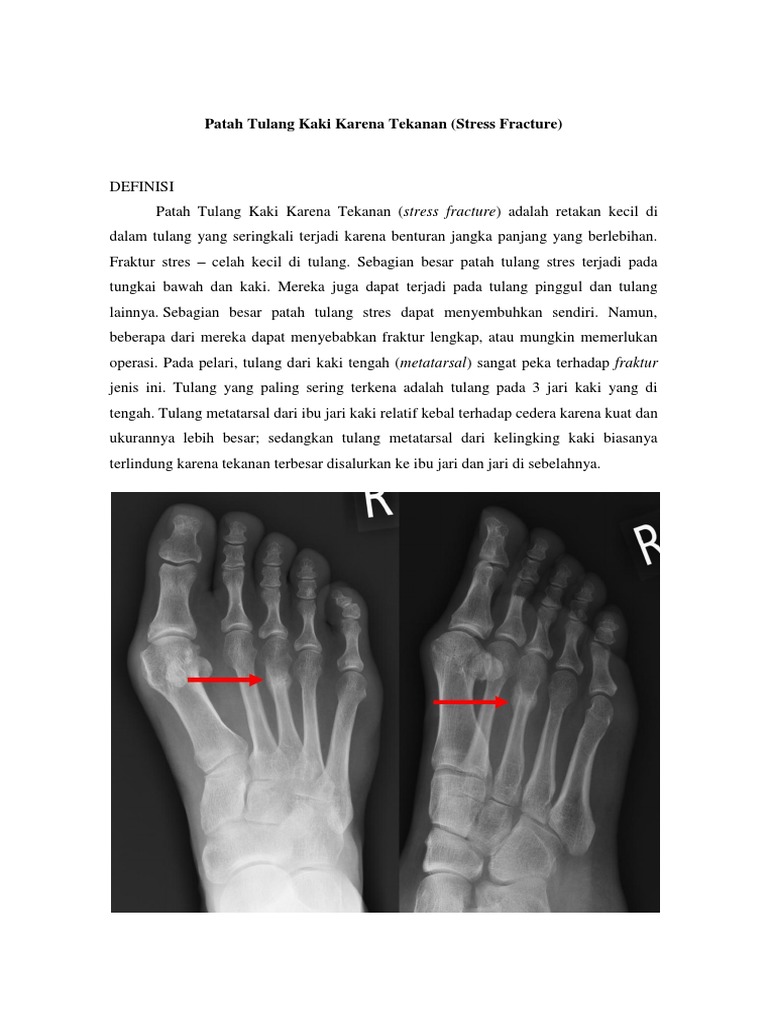

Fraktur Stres